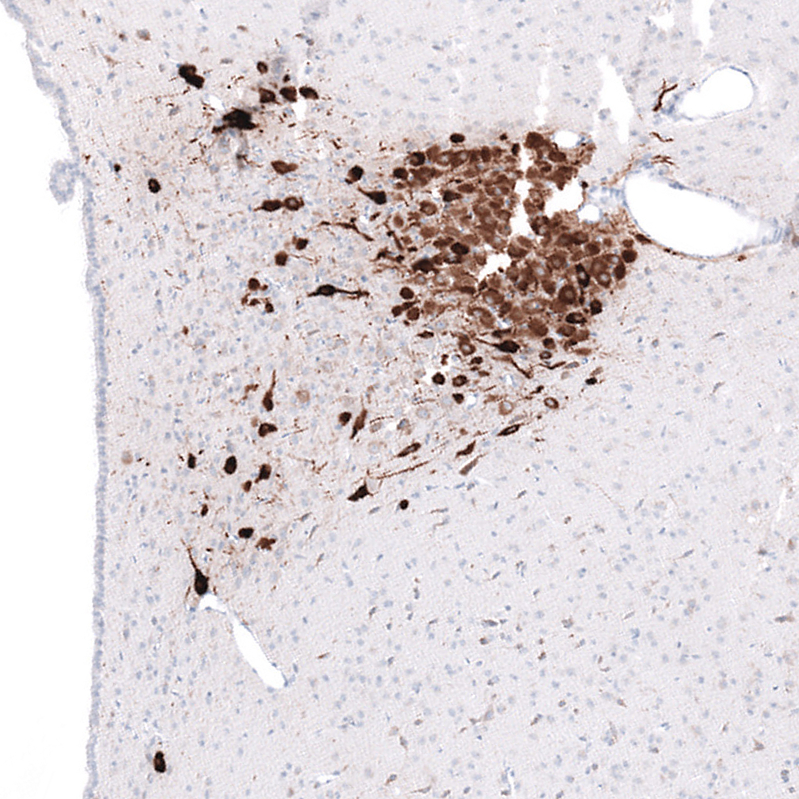

Immunohistochemical staining of rat paraventricular hypothalamic nucleus shows strong cytoplasmic positivity in neurons.